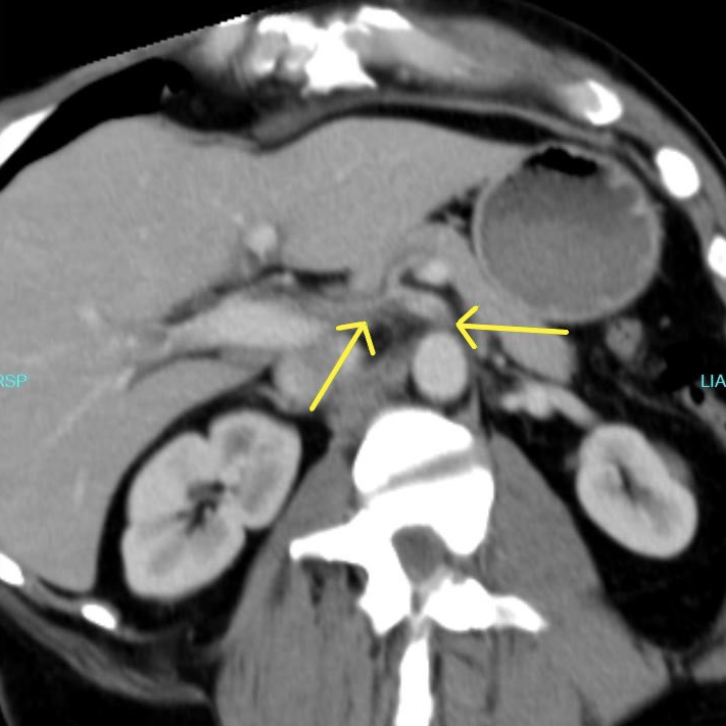

A contrast-enhanced CT scan was completed and revealed stenosis of the celiac trunk and mild bulbous dilatation of the post-stenotic celiac trunk (Figure 1). There was the appearance of a dissection flap that developed into an eccentric hypodense non-enhancing false lumen. This appeared to extend into the common hepatic arterial trunk and the splenic arterial branch, then continued to the splenic hilum (Figure 2 and Figure 3). In addition, there was a large splenic hypo-density involving almost one-third of the central spleen (Figure 4). The findings were consistent with an acute dissection of the splenic and hepatic arteries, along with splenic infarction of the central one-third of the spleen. A differential diagnosis of arcuate ligament syndrome was also considered, given the significant scoliosis seen on scout film of the CT scan (Figure 5).